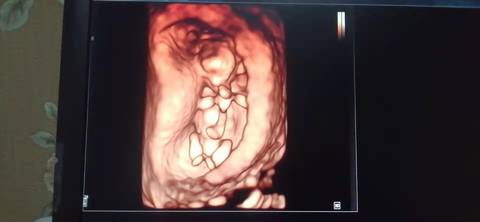

十二周的nt,是不是小棉袄啊? 医生给看宝宝腿的时候生殖器那里是平平的,是女宝吗?我和老公都挺想要小棉袄的

journal_insert_pic_1741079332journal_insert_pic_1741079455journal_insert_pic_1741080014journal_insert_pic_1741080182